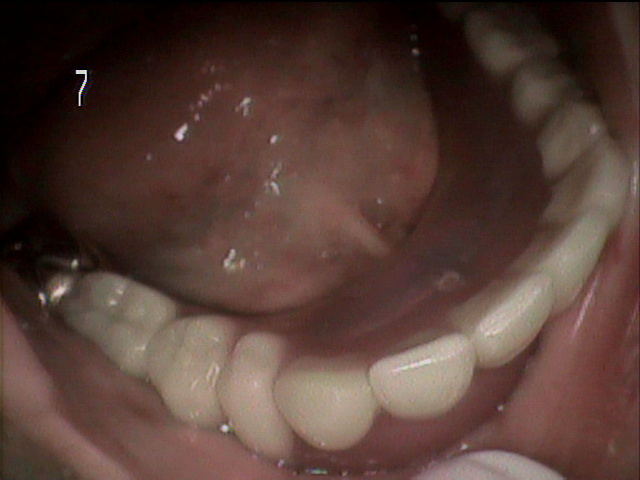

刈谷市半城土町よりお越しの 80歳女性の Iさんは、 毎月入れ歯と自分の歯をメンテナンスに通院されています。

刈谷市半城土町よりお越しの 80歳女性の Iさんは、 毎月入れ歯と自分の歯をメンテナンスに通院されています。

刈谷市今川町よりお越しの 85歳女性 Hさんは 上下共に総入れ歯です。ともに自費にて精密入れ歯を使用されていましたが、

刈谷市今川町よりお越しの 85歳女性 Hさんは 上下共に総入れ歯です。ともに自費にて精密入れ歯を使用されていましたが、